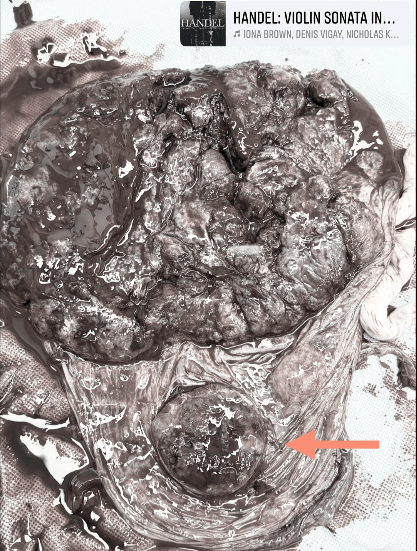

副胎盤(Succenturiate Placenta)

所謂的副胎盤

就是指一種胎盤異常的情況

就是在正常胎盤之外

還多了一個額外的小胎盤

透過血管跟主要胎盤相連

連我這種老鳥也很少見到這麼完整被拿出來的副胎盤

所以跟大家分享一下顆顆

(紅色箭頭指的地方就是副胎盤

(為降低不適感我把顏色盡量去掉了